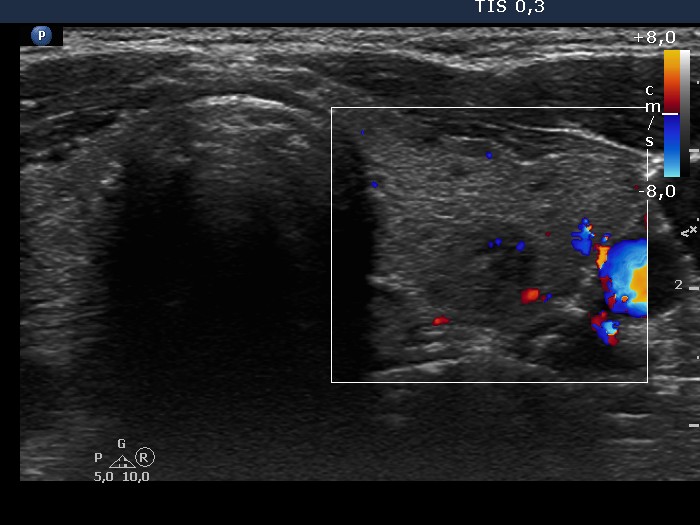

Consecutive patients with Hashimoto's thyroiditis - Case 24. (ultrasonographic picture 8)

Left lobe, horizontal scan, color Doppler mode. The hypoechogenic area displays signs of intralesional blood flow.